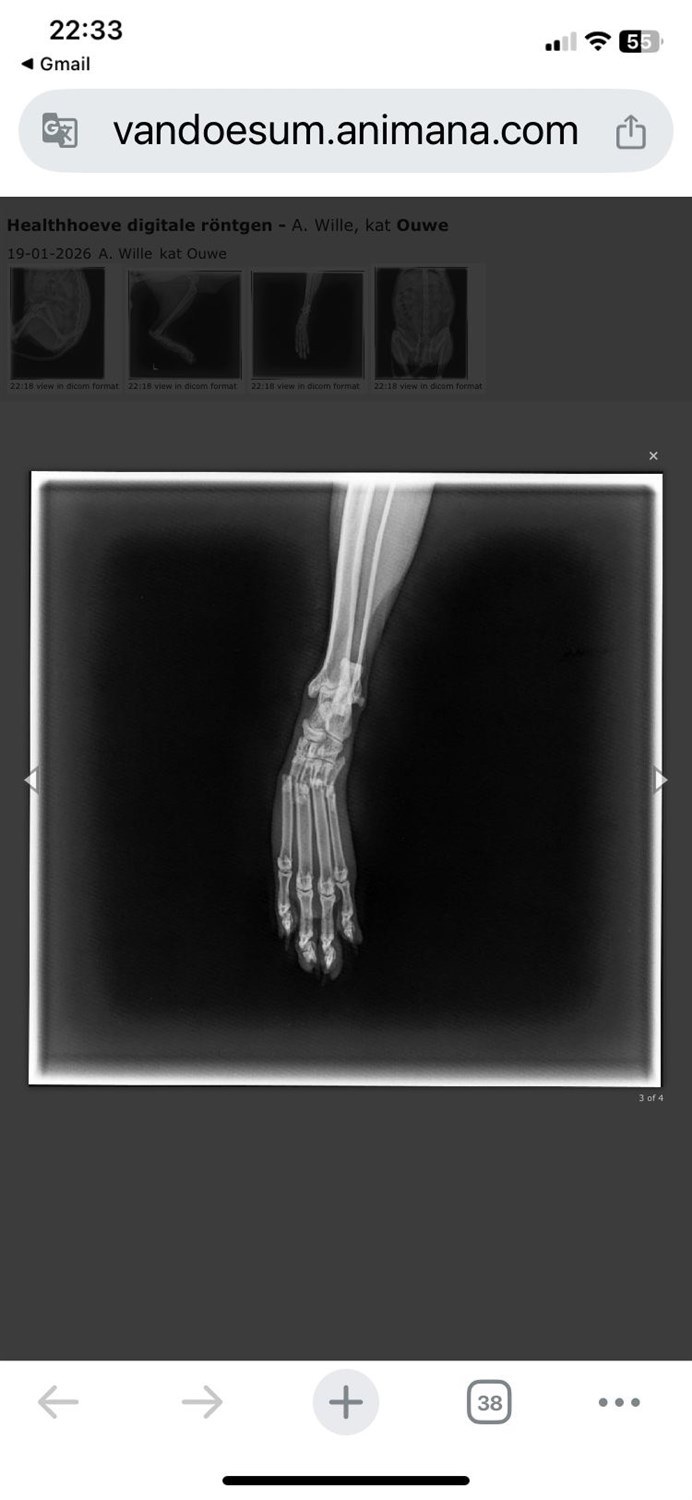

Na een narcose en foto's bleek dat je was aangereden en dat je achterpoot helemaal doormidden gebroken was 😞, ook aan je nagels was te zien dat je hebt gevochten voor je leven om terug naar je huisje te komen buiten, wat niet helemaal lukte.

Aangezien je nog erg vitaal bent, en de breuk gespalkt kon worden gaven zowel de dierenarts als ik dit een kans maar zaten hier begrijpelijk wel kosten aan verbonden.

En kun je voor nu proberen te herstellen met een spalk, al is dit niet voldoende en moet je geopereerd worden.. helaas en begrijpelijk kost dit wel wat geld..